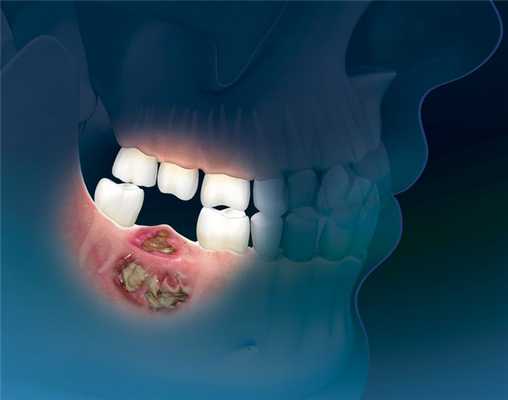

Заболевание развивается, когда опухоль локализуется на слизистой оболочке альвеолярного отростка или мягких тканях дна полости рта c переходом на кость.

Часто больные обращаются к врачу, когда опухоль уже достигает больших размеров, отмечается распад новообразования, зловонный запах изо рта, кровотечение. Их также могут беспокоить припухлости или язвы во рту, расшатывание и выпадение зубов, кровоточивость слизистой оболочки полости рта. Позднее присоединяются жалобы на затрудненное открывание рта, трудность или невозможность приема пищи, обилие слюны, похудание.